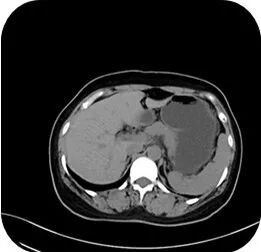

肝胆胰脾肾CT:肝囊肿;肝内钙化灶;胰腺形态饱满。